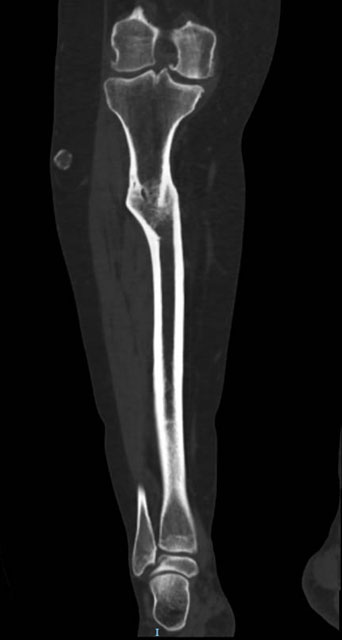

Management of a post-traumatic knee pain: Pre-op CT-scan

Pre-op CT-scan